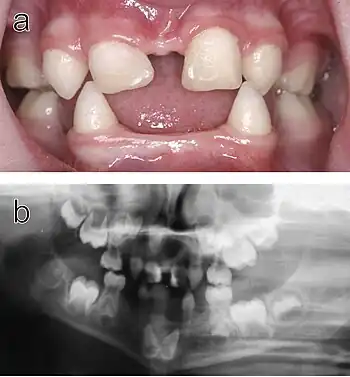

Ectodermal dysplasia is a rare but severe condition where the tissue groups (specifically teeth, skin, hair, nails and sweat glands) derived from the ectoderm undergo abnormal development. This is a diffuse term, as there are over 170 subtypes of ectodermal dysplasia. It has been accepted that the disease is caused by a mutation or a combination of mutations in certain genes. Research of the disease is ongoing, as only a fraction of the mutations involved with an ectodermal dysplasia subtype have been identified.[10]

.jpg.webp)

Hypohidrotic ectodermal dysplasia (HED) is the most common subtype of the disease. Clinical cases of patients with this condition display a range of symptoms. The most relevant abnormality of HED is hypohidrosis, the inability to produce sufficient amounts of sweat, which is attributed to missing or dysfunctional sweat glands. This aspect represents a major handicap particularly in the summer, limits the patient's ability to participate in sports as well as his working capacity, and can be especially dangerous in warm climates where affected individuals are at risk of life-threatening hyperthermia. Facial malformations are also related to HED, such as pointed or absent teeth, wrinkled skin around the eyes, a misshaped nose along with scarce and thin hair. Skin problems like eczema are also observed in a number of cases.[11] Most patients carry variants of the X-chromosomal EDA gene.[12] This disease typically affects males more severely because they have only one X chromosome, while in females the second, usually unaffected X chromosome may be sufficient to prevent most symptoms.